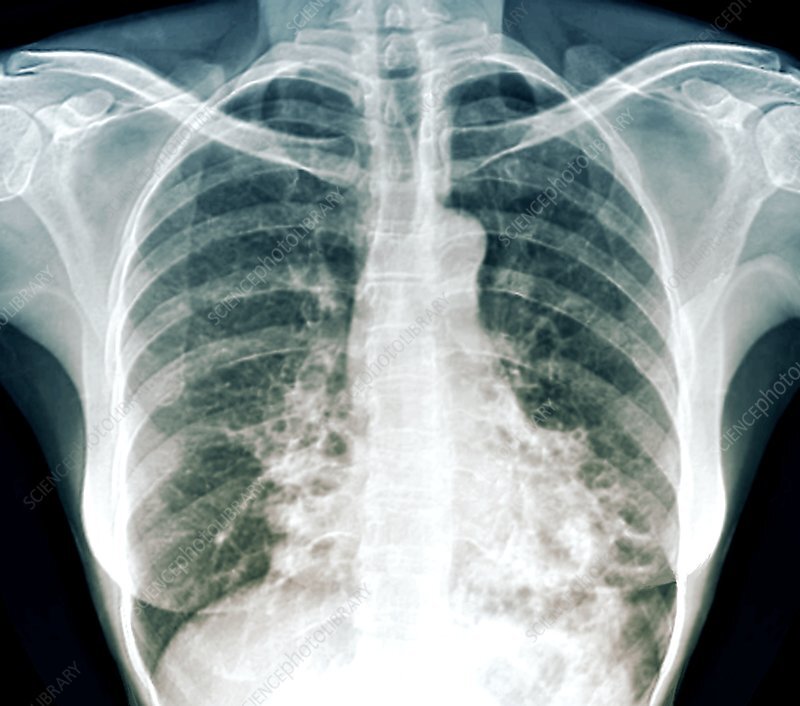

Diagnóstico radiológico de Bronquiectasias

A

-Radiografía con imágen dilatada en ríel

-Apergilosis broncopulmonar alérgica-Aspergillus fumigatus-asma, fibrosis quística